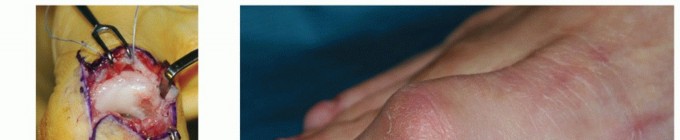

DEFINITION Turf toe injuries involve the capsular-ligamentous-sesamoid complex of the hallux metatarsophalang…

DEFINITION Hallux sesamoid bone fracture is a break through the sesamoid bone or cartilage. Medial sesamoid b…